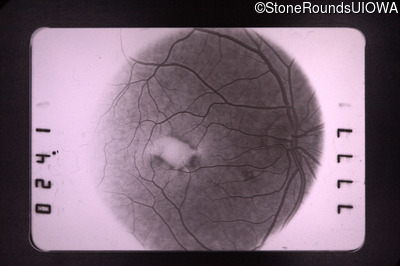

Pattern Dystrophy (IIC)

Fluorescein Angiography - Right - 20/70

Exemplar

Fluorescein Angiography - Left - 20/30 +1